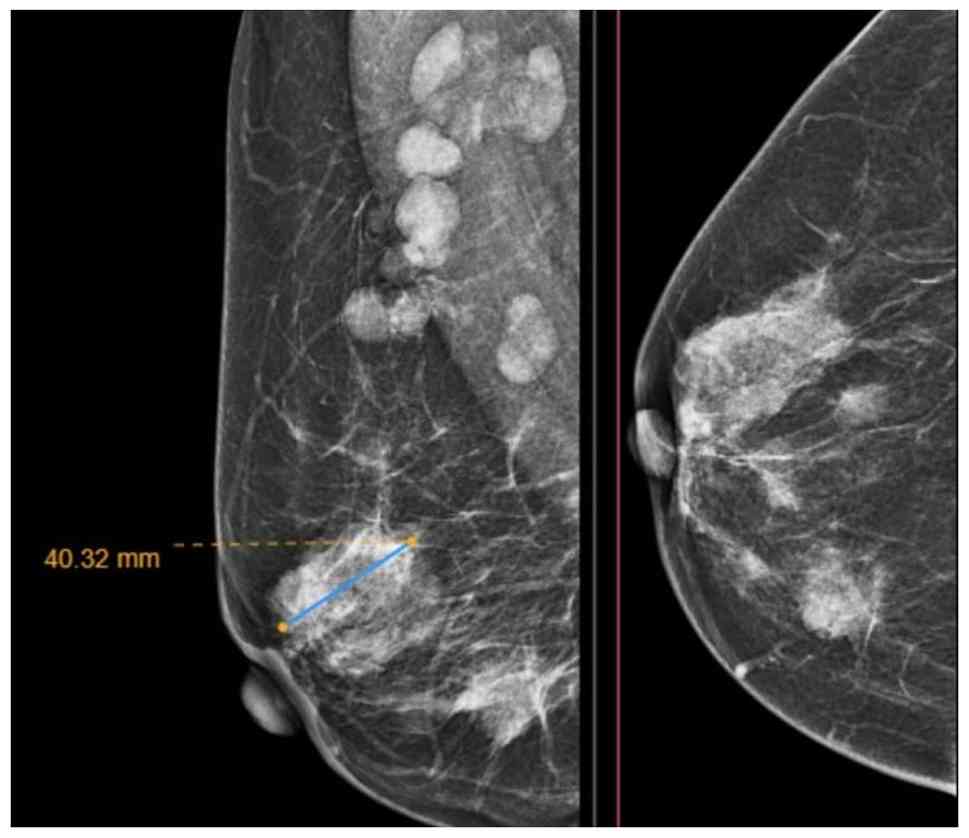

An abdominal ultrasound revealed bilateral renal staghorn stones, suggesting a possible underlying metabolic disorder, while the remainder of the examination did not reveal any notable findings. A breast mammography revealed multiple hyperdense masses with irregular margins throughout the right breast, with the largest lesion in the central region, measuring 40x32 mm. No microcalcifications were observed (Fig. 1). Right axillary lymph node involvement was also noted, with a small number of matted abnormal lymph nodes identified. The findings were classified as BIRADS-5. Although the ultrasound examinations was performed at the institution, the images were not available because they had not been digitally archived in the radiology database at the time of the examination. A core biopsy of the right breast mass and right axillary lymph node confirmed invasive PLC, grade II (moderately differentiated). The right axillary lymph node biopsy also revealed metastatic carcinoma (Fig. 2). Immunohistochemical analyses were performed on formalin-fixed, paraffin-embedded tissue. Sections at a thickness of 4-6 µm were prepared from paraffin blocks, mounted on charged slides and incubated overnight at 60˚C. Heat-induced antigen retrieval was carried out using the Dako PT Link system (Agilent Technologies, Inc.) at 100˚C for 5-10 min, employing either citrate buffer (pH 6.0) or Tris-EDTA buffer (pH 9.0) according to the antibody used. Following antigen retrieval, the slides were rinsed for 15 min at room temperature in Tris-buffered saline containing 0.05% Tween-20 (0.05 mol/l Tris/HCl, 0.15 mol/l NaCl; pH 7.6). The tissue sections were then demarcated using a hydrophobic pen, and endogenous peroxidase activity was quenched with 3% hydrogen peroxide. Primary antibodies directed against ER, PR, HER2, Ki-67 and E-cadherin were applied using the following reagents: ER (rabbit monoclonal, clone SP1; cat. no. RM-9101-S; Thermo Fisher Scientific, Inc.; dilution 1:100), PR (mouse monoclonal, clone PgR636; cat. no. M3569; Agilent Technologies, Inc.; dilution 1:100), HER2 (rabbit monoclonal, clone 4B5; cat. no. 790-2991; Roche Diagnostics; ready-to-use), Ki-67 (mouse monoclonal, clone MIB-1; cat. no. M7240; Agilent Technologies, Inc.; dilution 1:200) and E-cadherin (mouse monoclonal, clone NCH-38; cat. no. M3612; Agilent Technologies, Inc.; dilution 1:100). All antibodies were diluted in the manufacturer's antibody diluent and incubated for 80 min at room temperature (20-25˚C). Detection was achieved using a horseradish peroxidase-linked secondary antibody (EnVision™ FLEX HRP polymer detection system; cat. no. SM802; Agilent Technologies, Inc.; ready-to-use, no dilution) and 3,3'-diaminobenzidine (DAB) chromogen, each incubated for 15 min at room temperature (20-25˚C). Counterstaining was performed with Gill II hematoxylin for 30 sec at room temperature, after which the slides were dehydrated and coverslipped. Immunostaining results demonstrated strong nuclear ER expression with an Allred score of 8 (3 + 5) and PR positivity with an Allred score of 4 (2 + 2). HER2 staining was negative (score 1), and the Ki-67 labeling index was approximately 22%. The loss of E-cadherin expression in tumor cells was observed, consistent with ILC.

Full-field digital mammography of the

right breast (mediolateral oblique and craniocaudal views)

revealing multiple heterogeneously dense masses in different

quadrants, the largest measuring 40 mm in the central lateral

region.

Figure 1

Full-field digital mammography of the right breast (mediolateral oblique and craniocaudal views) revealing multiple heterogeneously dense masses in different quadrants, the largest measuring 40 mm in the central lateral region.